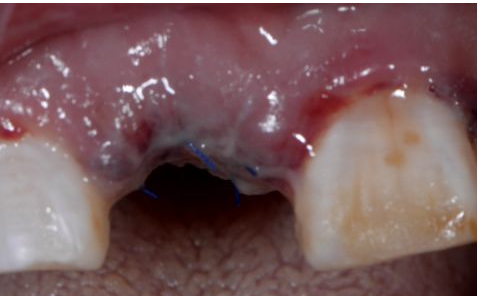

植入后縫合